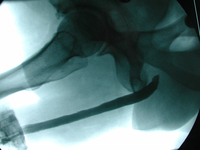

Das retrograde Urethrozystogramm zeigt das Operationsergebnis nach offener Harnröhrenrekonstuktion bei langstreckiger Harnröhrenstriktur